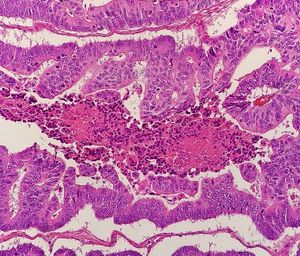

5. 1. 조직병리학

생검 또는 수술로 채취한 조직을 분석하여 종양의 조직병리학적 특성을 확인한다. 병리 보고서에는 종양 세포의 현미경적 특성, 종양이 건강한 조직으로 침투하는 양상, 종양의 완전 제거 여부 등이 기술된다. 대장암의 가장 흔한 형태는 선암종으로, 전체 대장암의 95%[84]에서 98%[85]를 차지한다. 드물게 림프종, 선편평세포암, 편평 세포 암종 등이 발생할 수 있으며, 일부 아형은 더 공격적이다.[86] 불확실한 경우에는 면역조직화학 검사를 시행할 수 있다.[87]